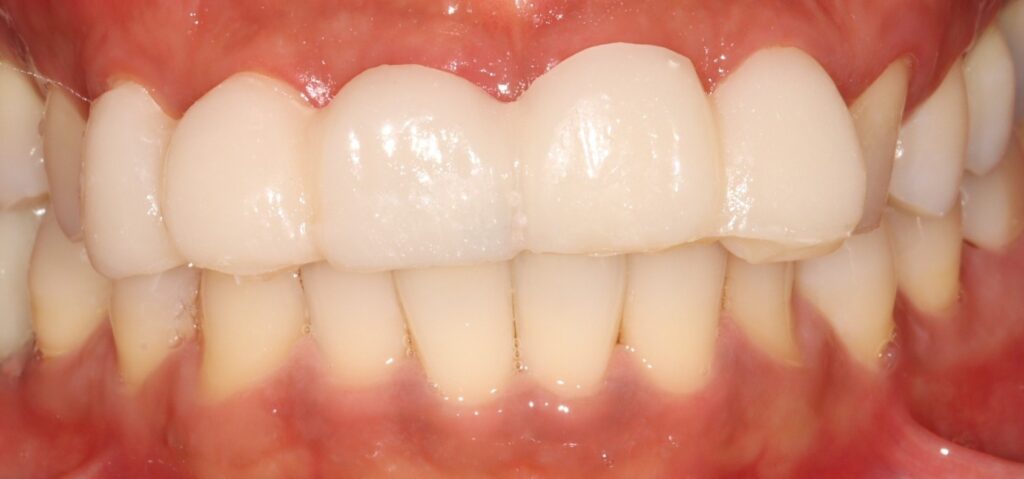

이제부터 예시 사진을 보면서

진료 과정을 소개해 드리도록 하겠습니다.

예시 사진을 보면

앞니의 2/3이상이 부러져 사라진 것을

확인할 수 있는데요.

2025.02.12

그로 인해 11번의 경우

자연치 내부 치수가 드러난 것을

볼 수 있으며,

21번은

치수가 드러나지 않았지만

많은 양의 치질이 사라져 있습니다.

이후 부러진 뼈가 치유될 수 있게

잠간고정술로 고정하여

치유를 도와줍니다.

치유를 되는 동안

임시치아를 제작하여

생활에 불편함이 없도록

도와줍니다.